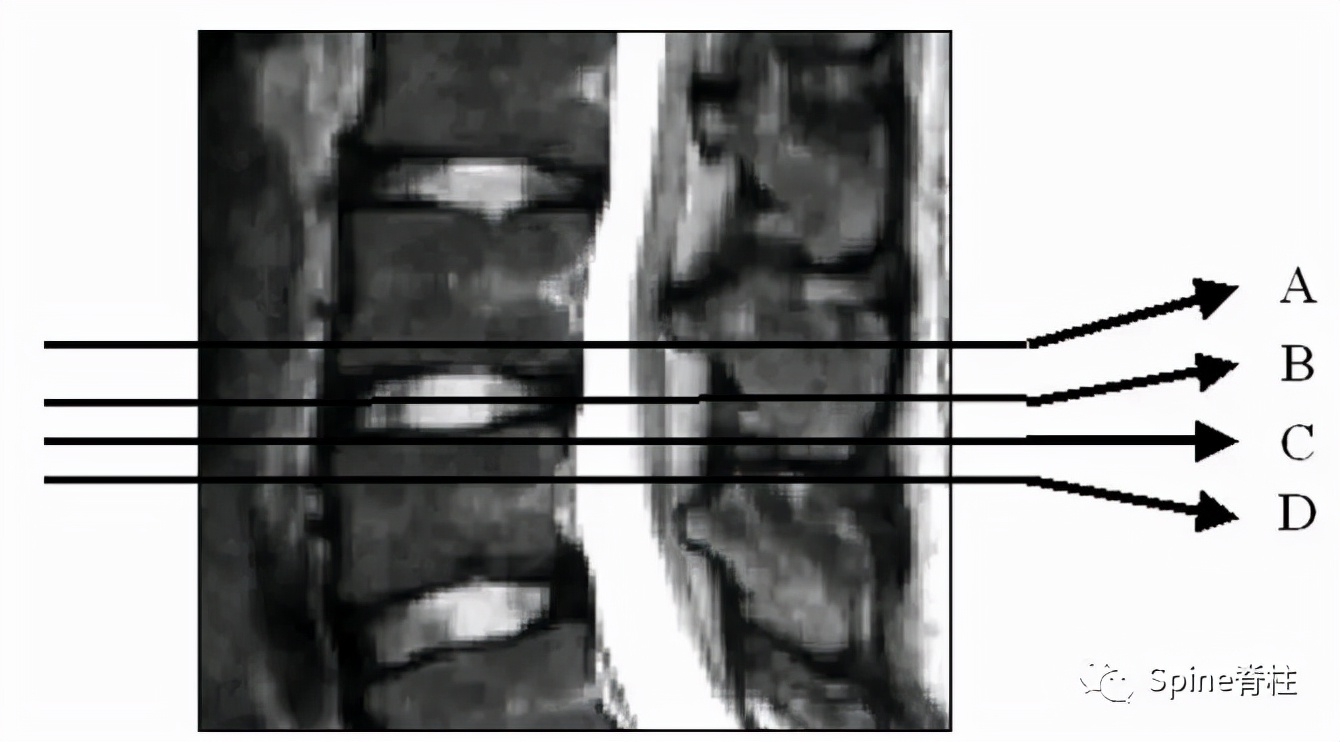

因此, Sairyo教授也提出,对于青少年腰痛患者行MRI检查时,在传统椎间盘层面的基础上(A-C线), 多加一个经椎弓根层面(D线) (影像科医生希望能看到) 。因为,A-C线椎间盘层面可很好看出青少年腰椎间盘突出和腰椎椎体后缘离断症,而D线经椎弓根层面可以早期诊断出腰椎峡部裂和腰椎椎弓根损伤。